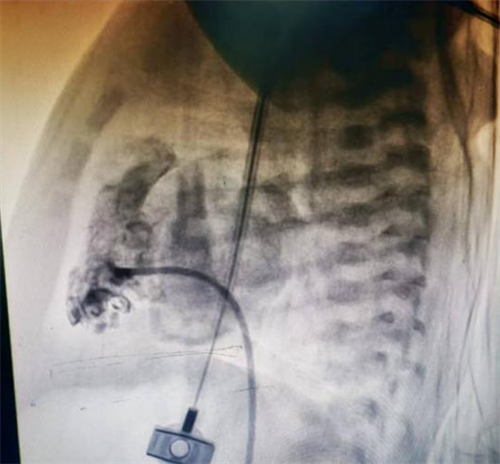

图中严重狭窄的肺动脉瓣

手术室内,麻醉团队为手术精准护航,新生儿科刘红副主任医师全程严密监护生命体征,守住安全底线。小儿心脏科张庆彪主任团队在影像引导下,凭借高超技术,仅依靠一根微导丝建立轨道,成功将球囊导管送至狭窄的肺动脉瓣处。随着球囊的扩张,原本近乎闭锁的瓣膜被成功打开。术后即时测量显示,跨瓣压差从术前的127mmHg大幅降至12mmHg,患儿血氧饱和度随即显著改善,手术宣告成功。